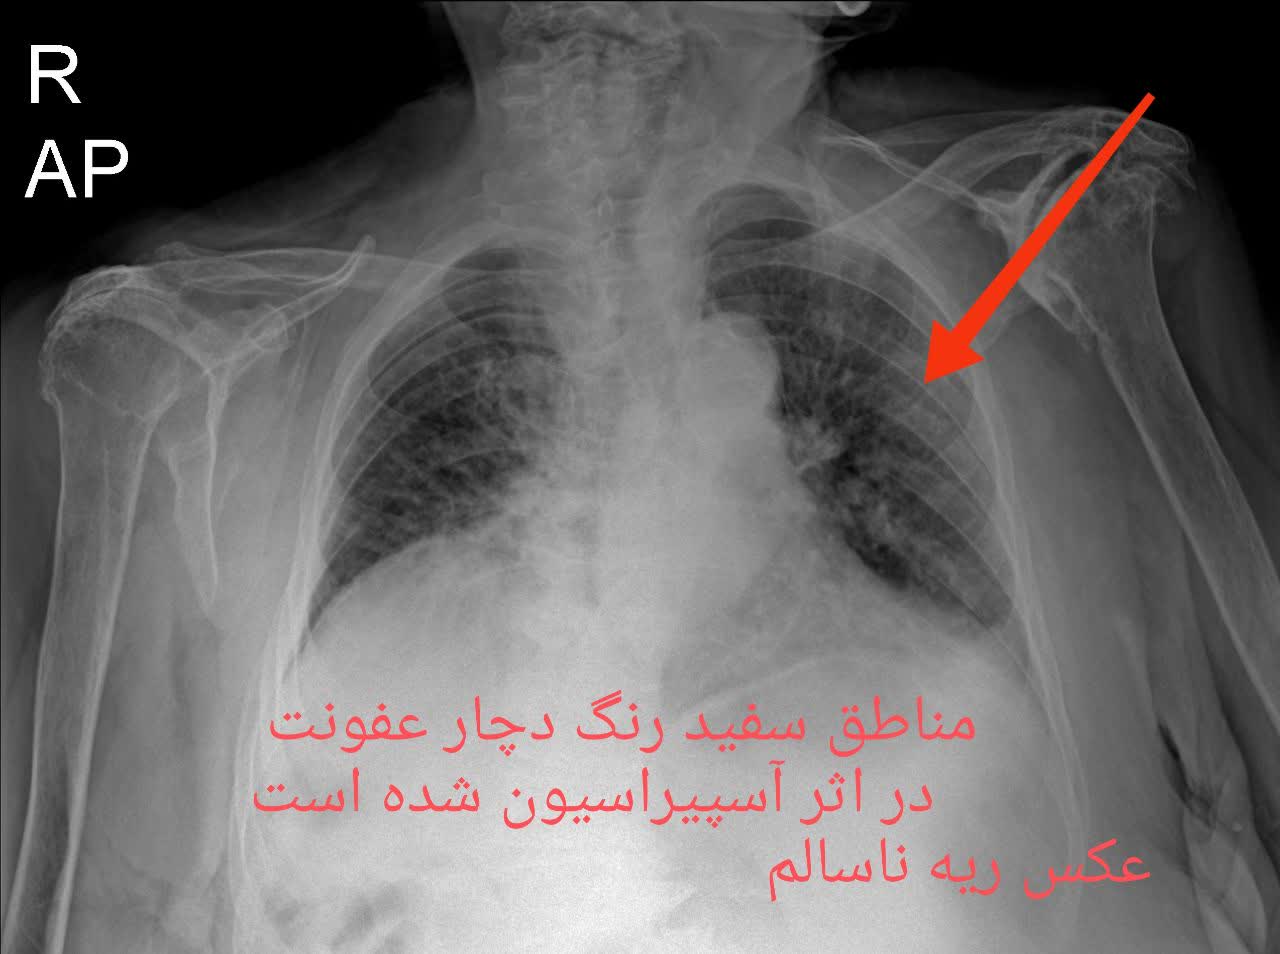

مقایسه عکس ریه سالم و ناسالم

در عکس ریه سالم و ناسالم، تفاوتها معمولاً با چشم غیرمسلح نیز مشهودند. ریه سالم تصویری یکنواخت و شفاف دارد، با خطوط ریوی طبیعی و بدون سایه یا توده. در مقابل، ریه ناسالم ممکن است سایههای غیرطبیعی، نواحی سفید شده (indicative of consolidation)، خطوط پررنگتر ناشی از فیبروز یا تودههای نامنظم را نمایش دهد. تشخیص این تفاوتها توسط پزشک رادیولوژیست، نیاز به تجربه و تجهیزات باکیفیت دارد، چیزی که در خدمات رادیولوژی ریه در منزل تهران و رادیولوژی ریه در منزل کرج فراهم شده است.